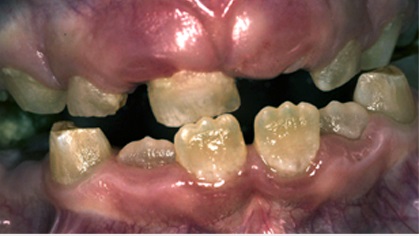

L’amélogénèse imparfaite, relativement fréquente, touche surtout les dents temporaires.

Amélogénèse imparfaite du groupe incisivo-canin lactéal chez un enfant de 18 mois.